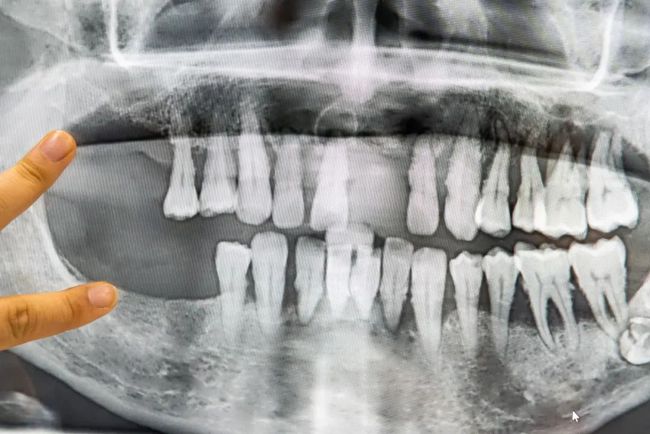

多颗缺失

种植后